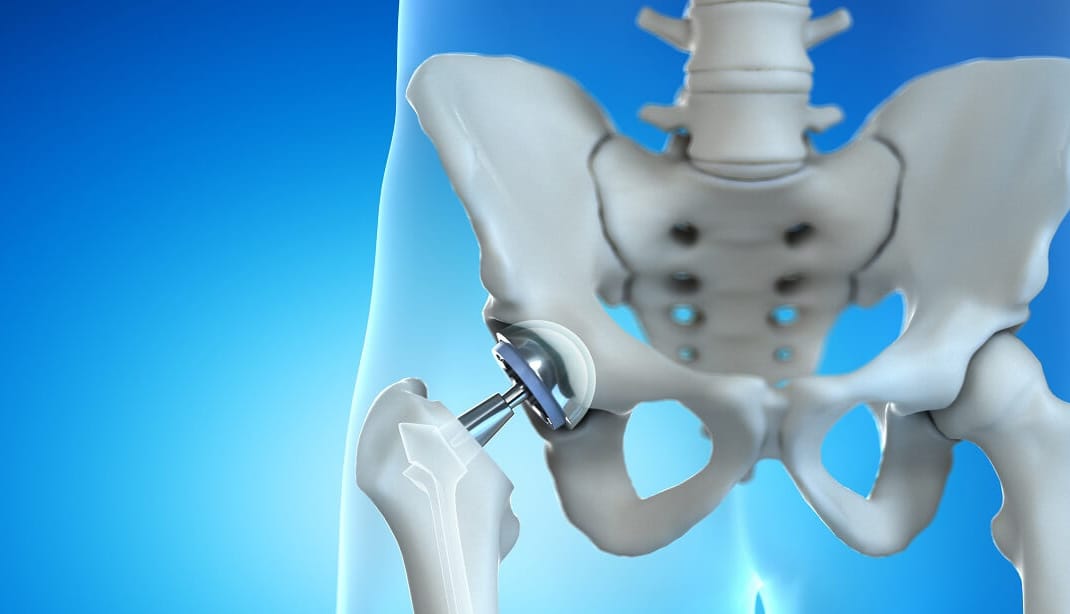

- إذا كانت كل هذه الطرق السابقة غير ناجحة ومازال المريض يشعر بالألم، في هذه الحالة يلجأ الطبيب إلى إجراء عملية جراحية في المفصل نفسه ولكن يكون هذا القرار هو القرار الأخير وبعد تجربة كل الطرق السابقة.